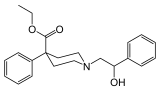

4-Phenylpiperidines

Others

Structures

Picenadol Picenadol |